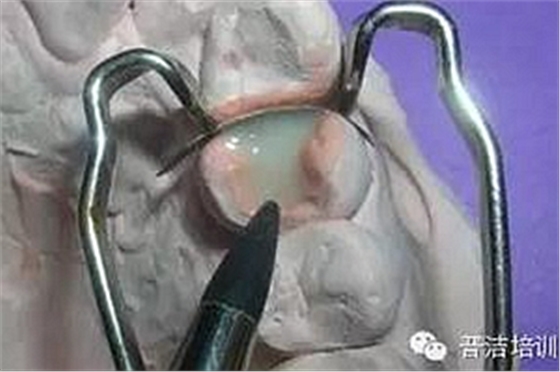

完全就位后噴砂清潔組織面

牙線去除鄰面樹脂粘結(jié)劑

鄰面拋光

粘結(jié)完成后